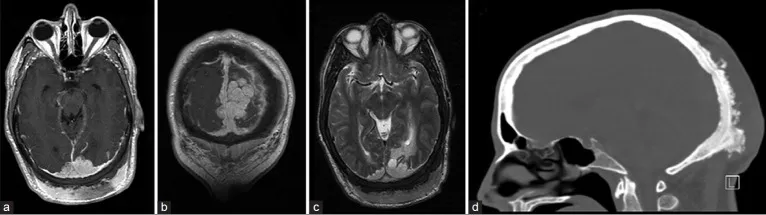

48岁男性患者因头痛加剧伴视物模糊3天就诊。术前影像学检查显示窦汇区存在约11.5厘米的轴外占位性病变,增强扫描呈现明显强化特征。脑血管造影检查证实病变导致上矢状窦、窦汇及左侧横窦近端发生闭塞,皮质静脉通过Labbe静脉实现引流功能,深部引流则依赖枕窦完成。体格检查发现患者存在下方视野偏盲症状,枕后部可触及巨大坚硬隆起,表面皮肤未见异常表现。

术前诊断性检查包括头颅磁共振成像(MRI)及磁共振血管成像(MRA),结果显示直径11.5厘米的肿瘤病灶跨越幕上及幕下区域,向双侧顶叶与枕叶延伸,并侵犯上矢状窦、窦汇及横窦近端。肿瘤经颅骨侵犯至枕部头皮及真皮层。脑血管造影显示上矢状窦、窦汇及横窦近端部分节段血流消失,深部静脉经枕窦引流,皮质静脉经增粗的Labbe静脉引流。